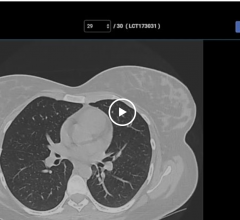

March 18, 2021 — Medicare lung cancer screening coverage should be updated to reflect new U.S. Preventive Services Task ...